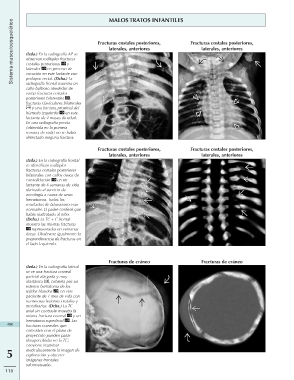

(Izda.) En la radiografía AP se Fracturas costales posteriores, Fracturas costales posteriores,

observan múltiples fracturas laterales, anteriores laterales, anteriores

costales posteriores y

laterales en proceso de Fracturas costales posteriores, Fracturas costales posteriores,

curación en este lactante con laterales, anteriores laterales, anteriores

prolapso rectal. (Dcha.) La

radiografía frontal muestra un Fracturas de cráneo Fracturas de cráneo

callo bulboso alrededor de

varias fracturas costales

posteriores bilaterales ,

fracturas claviculares bilaterales

y una fractura proximal del

húmedo izquierdo en este

lactante de 2 meses de edad.

En una radiografía previa

(obtenida en la primera

semana de vida) no se había

detectado ninguna fractura.

(Izda.) En la radiografía frontal

se identifican múltiples

fracturas costales posteriores

bilaterales con callos óseos de

consolidación en un

lactante de 6 semanas de vida

derivado al servicio de

oncología a causa de unos

hematomas. Todos los

resultados de laboratorio eran

normales. El padre confesó que

había maltratado al niño.

(Dcha.) La TC + C frontal

muestra las mismas fracturas

representadas en ventanas

óseas. Obsérvese igualmente la

preponderancia de fracturas en

el lado izquierdo.

(Izda.) En la radiografía lateral

se ve una fractura craneal

parietal alargada y muy

diastásica , cubierta por un

extenso hematoma de los

tejidos blandos , en este

paciente de 1 mes de vida con

numerosas lesiones costales y

metafisarias. (Dcha.) La TC

axial sin contraste muestra la

misma fractura craneal y un

hematoma superficial . Las

490 fracturas craneales que

coinciden con el plano de

proyección pueden pasar

desapercibidas en la TC;

conviene examinar

5 meticulosamente la imagen de

exploración y obtener

imágenes frontales

reformateadas.